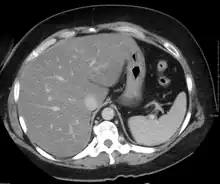

Imaging studies are often obtained during the evaluation process. Ultrasonography reveals a "bright" liver with increased echogenicity. Medical imaging can aid in diagnosis of fatty liver; fatty livers have lower density than spleens on computed tomography (CT), and fat appears bright in T1-weighted magnetic resonance images (MRIs). Magnetic resonance elastography, a variant of magnetic resonance imaging, is investigated as a non-invasive method to diagnose fibrosis progression.[30] Histological diagnosis by liver biopsy is the most accurate measure of fibrosis and liver fat progression as of 2018.[8] Conventional imaging methods, such as ultrasound, CT and MRI, are not specific enough to detect fatty liver disease unless fat occupies at least 30% of the liver volume.[31]